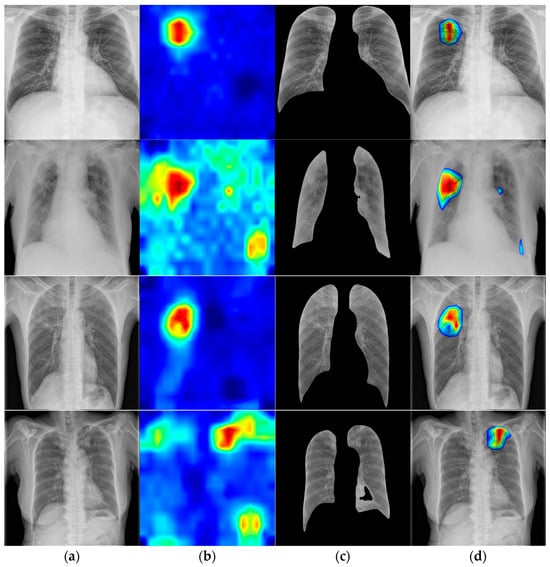

- Heatmap-based visualization of lesion locations to find pathological features;

3.5. Visualization